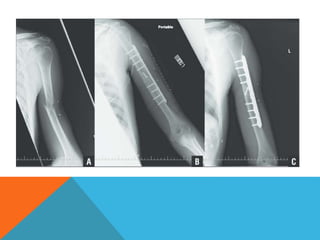

COMPRESSION WITH OVERBANDING

 If a straight plate is

tensioned on a straight

bone, a transverse

fracture gap will open

up due to the eccentric

forces acting on the

opposite side.

 If the plate is slightly

prebent prior to the

application (a), the gap

in the opposite cortex

will disappear as

compression is built up

(b), so that finally the

whole fracture is firmly

closed and compressed

(c).